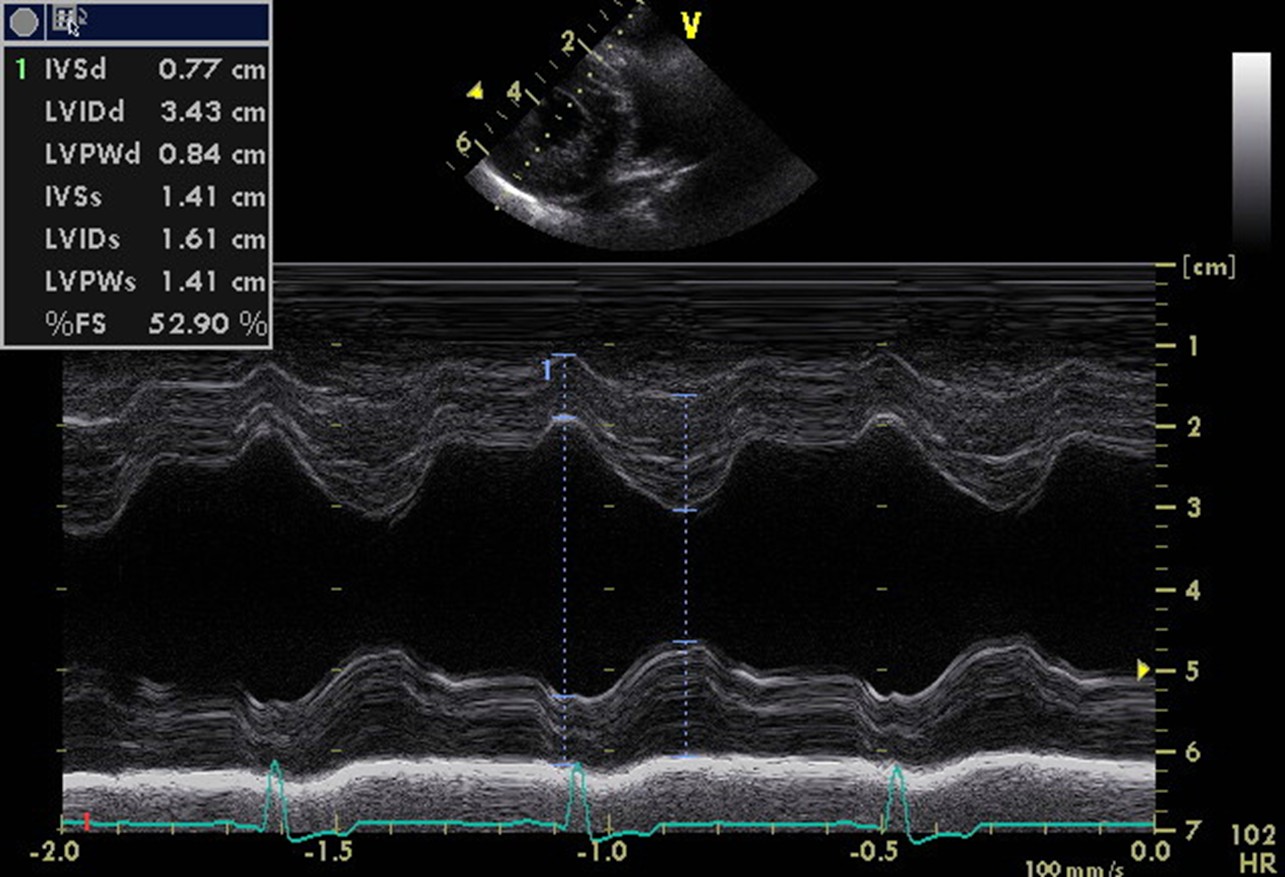

Echo image of the right parasternal short axis view at the level of the chordae tendineae – used to create the M-mode image for measurement of the LV internal diameter in systole and diastole.